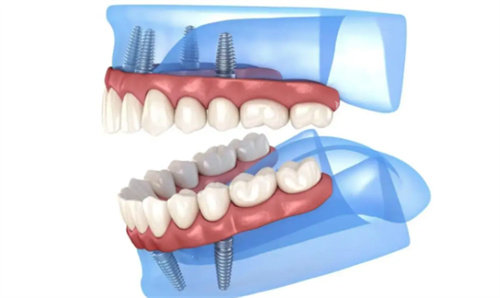

该机构在术前检查阶段使用三维影像设备辅助设计,帮助患者更直观了解牙槽骨状况。针对复杂病例(如全口修复),团队倾向于分阶段操作,优先修复咬合功能再完善美学成效。术后定期安排复查,跟踪种植体稳定性。